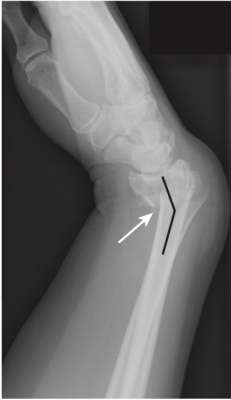

- Gãy Smith: gãy đầu dưới xương quay với đầu gãy di lệch gập góc gan tay (đối ngược với gãy Pouteau-Colles). Nguyên nhân là do ngã lên mu bàn tay gập (Hình 11).